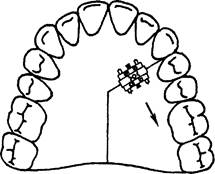

При равномерном сужении левой и правой половины зубного ряда целесообразно применять расширяющую пластинку с расположением винта на уровне срединного небного шва (рис. 13.36). При необходимости перемещения одного зуба или группы зубов в трансверсаль-ном направлении изготавливают пластину с секторальным распилом на верхнюю челюсть (рис. 13.37). При более значительном сужении переднего участка зубного ряда следует использовать расширяющую пластинку с петлей для ограничения расширения боковых участков зубного ряда (рис. 13.38).

Рис. 13.36. Расширяющая пластинка на верхнюю челюсть.

Рис. 13.37. Пластинка на верхнюю челюсть с секторальным распилом для перемещения одного зуба или группы зубов.